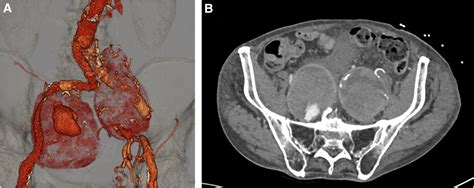

• Computed Tomography Angiography (CTA): This imaging test provides detailed images of the blood vessels and can help determine the size and location of the aneurysm.

• abdominal aortic aneurysm iliac artery

Successful repair of an arteriovesical fistula as a complication after ...

1702×1639